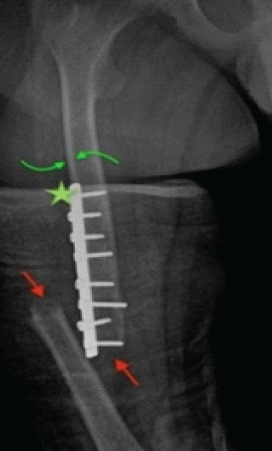

Harnessing 3D Printing Technology for Complex Acetabular Reconstruction in Revision Total Hip Arthroplasty: From Childhood Hip Trauma to Customized Modern Solutions